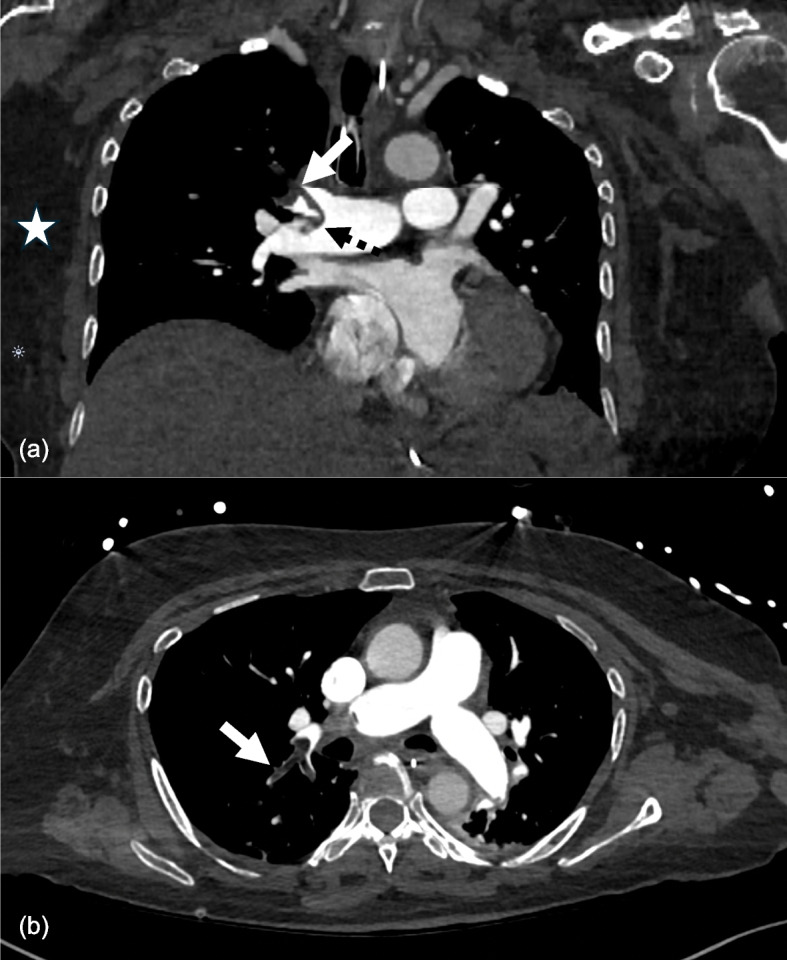

A CT pulmonary angiogram showed multiple pulmonary emboli involving the distal right main pulmonary artery and right upper lobe proximal segmental branches (Fig. 1). The density values of these emboli were between −80 and −100 Hounsfield units, compatible with macroscopic fat. There was imaging evidence of right heart strain with bowing of the interventricular septum and an enlarged pulmonary arterial trunk. The calculated RV/LV ratio was 3.39. A transthoracic echocardiogram demonstrated multiple features of right heart dysfunction, including a dilated right ventricle with severely impaired contraction, McConnell’s sign, and a D-shaped left ventricle. Her cardiac troponin I was elevated, peaking at 7863 ng/L. This was measured with the Abbott high sensitivity assay, with a reference range of < 16 ng/L, based on the gender-specific 99th percentile for women.

Fig. 1.

CT pulmonary angiogram. a Coronal soft tissue window demonstrating straddling pulmonary embolism within the right lobar and proximal segmental upper lobe branch (black dotted arrow). The filling defect in the right upper lobe lobar artery (white arrow) is of similar density to chest wall subcutaneous fat (white star). b Axial soft tissue window demonstrating the heterogeneous appearance of the embolus, suggesting admixed bland thrombus (white arrow)